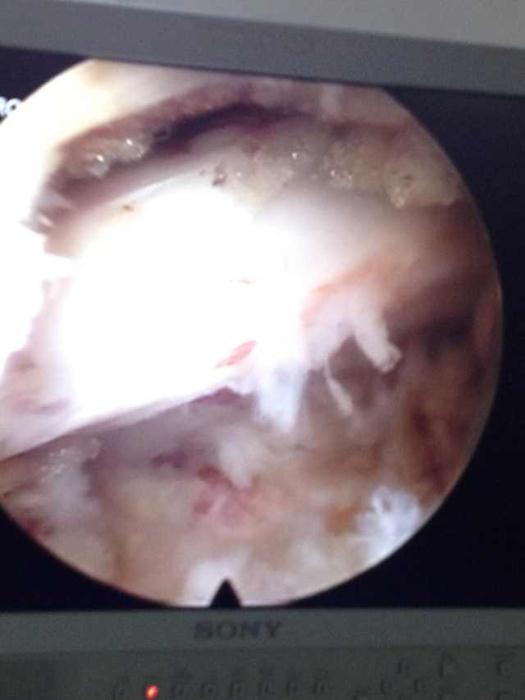

图4:A突出物

如今,在疼痛病房经常看到患者脸上洋溢着满意的笑容。占恭豪主任说,上述三位患者的腰椎都是巨大突出,张先生的突出物似门帘下垂;李先生的腰椎突出物似尾巴上翘,陈公公的是两节的腰椎巨大突出,神经都严重的受压,导致日常活动明显受限,生活质量严重下降。

腰椎间盘突出症的原因是腰椎骨中央髓核从包围它的纤维环裂口往外涌,形成一个凸起物,压迫腰椎神经,引起腰腿疼痛及麻木感,如果拖延下去,可导致下肢麻木发凉、酸困不适、抽筋、腿部肌肉萎缩、力量减弱、下肢不能抬离、甚至大小便异常。椎间孔镜就是在内窥镜下,使用抓钳摘除突出的组织。